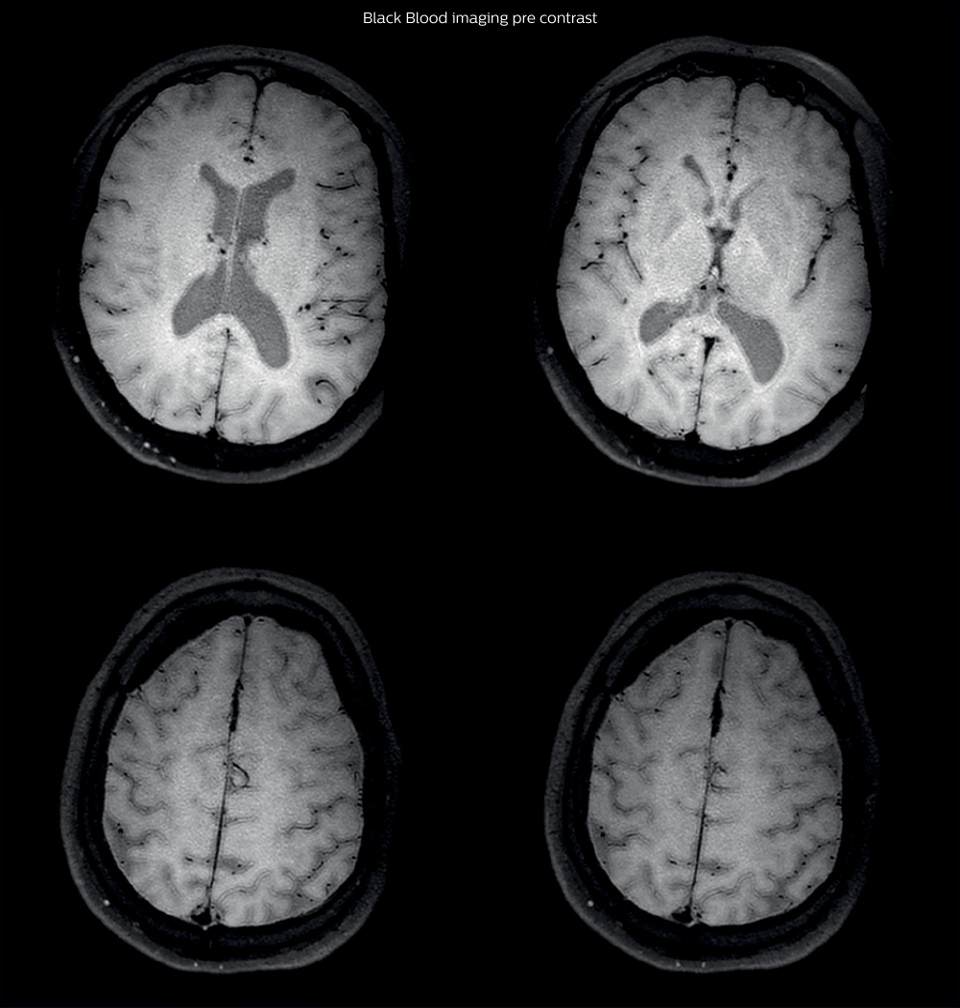

After a conventional routine MR imaging examination, the suspicion of vasculitis arose, therefore we performed an MRI including Black Blood imaging in a separate session. The dedicated ExamCard includes diffusion, FLAIR, MR angiography using TOF, and 3D T1 MRA with bolus injection. This ExamCard also includes Black Blood imaging before and after contrast. This examination was performed on our Ingenia 3.0T. Black Blood scan time 4:39 min, acquired voxel size 0.75 x 0.75 x 1.0 mm, 21 slices.

On FLAIR images we can see some nonspecific high signal abnormalities in frontal white matter bilaterally. On DWI we can see acute ischemic lesions which appear with high signal intensity. Arrows show vessel wall enhancement which appears concentric and homogeneous in different cerebral territories.

On the routine MR sequences that we did, we could see acute ischemic lesions. We see them very well on the diffusion images, where acute ischemic lesions usually appear with high signal intensity and restricted diffusion. However, the etiology of these lesions cannot be derived from these images. An area of restricted diffusion was seen in the anterior cerebral artery territory and we concluded it was an ischemic lesion. On MR angiography we can just see if there is stenosis or vessel occlusion, but it does not provide us information on the etiology of this kind of lesion. So, we decided to perform Black Blood imaging. The presence and the pattern of vessel wall enhancement on Black Blood imaging, can help us to determine the etiology of the lesion. differentiate vasculitis from other causes of vasculopathy, such as atherosclerosis, with a high specificity [1-3]. In an atherosclerotic lesion, vessel wall thickening and enhancement are usually eccentric, while in vasculitis the wall thickening and enhancement are usually concentric, homogenous, and in a long portion of the vessel. of patients whenever their treatment is installed in order to determine the efficacy of a particular treatment. In this case the Black Blood imaging helped us to suggest the diagnosis of HIV-related brain vasculitis.

Black Blood imaging can help us to noninvasively visualize vessel

wall thickening and enhancement patterns that occur in vasculitis, and help us distinguish it from atherosclerotic lesions. Imaging techniques such as time-of-flight (TOF) MR angiography are not very sensitive or specific for this kind of lesions. Other possible diagnostic methods are intra-arterial angiography or brain biopsies which are both invasive.